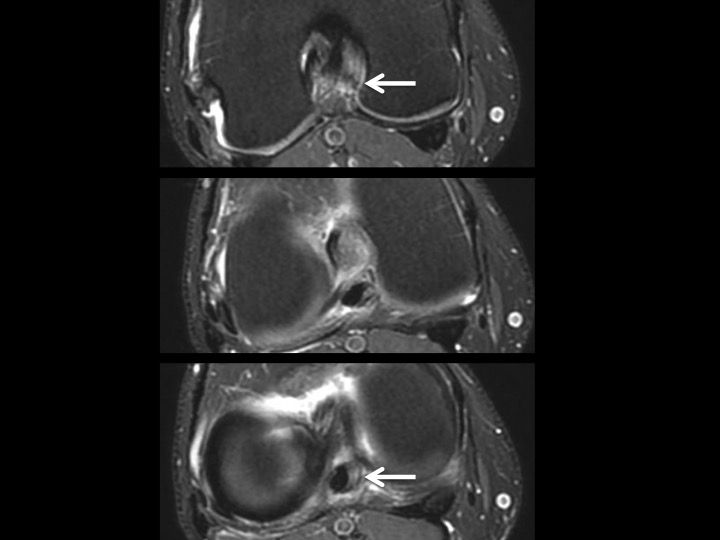

35M pain and swelling 1 month after fall playing basketball

There is intermediate signal soft tissue thickening along the medial aspect of the PCL with what appears to be a tear near the tibial insertion of the posteromedial bundle in the Sag images. The larger anterolateral bundle is intact, with minimal increased intrasubstance signal in the vertical segment. This is an isolated injury, so it will certainly be treated conservatively. I know there has been controversy over soft tissue thickening in this location, with reports of synovial thickening/scarring with intact PCL. Note that the opposite knee does not look like this (image 5). Even though this should heal with stability, I wonder if this might be the cause of scarring we sometimes see in this location and if it might not be a source of chronic pain and limitation. Thoughts? Reference article.

posteromedial bundle of posterior cruciate ligament ( RID2786 )